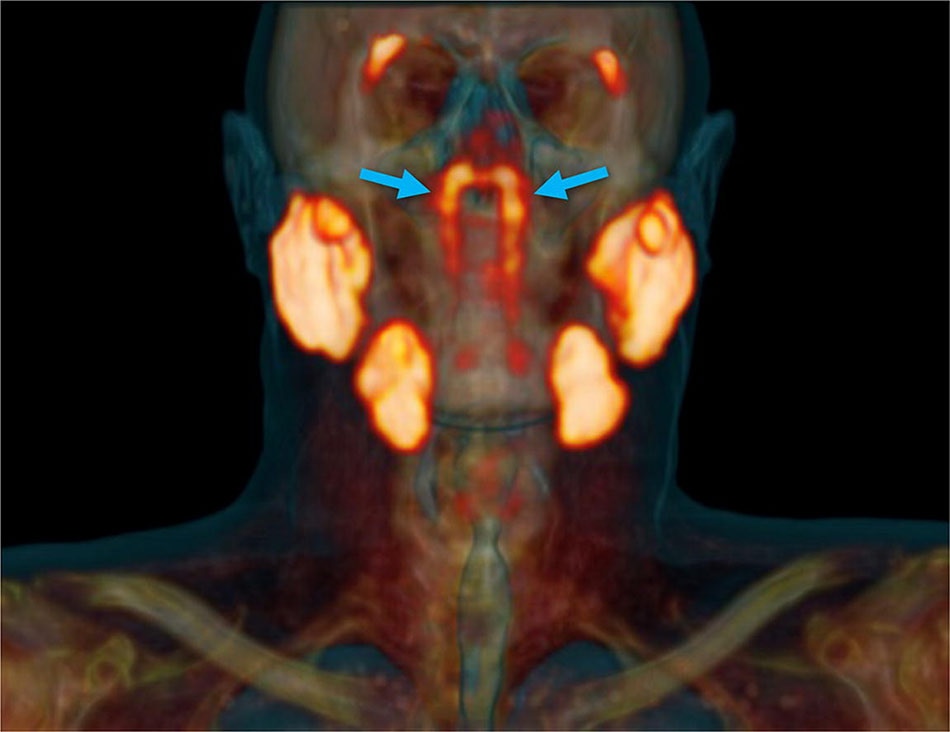

वैज्ञानिकों ने इंसानी शरीर में एक नए अंग का पता लगाया है. नीदरलैंड के वैज्ञानिक एक नए 'कैंसर स्कैन' की जांच कर रहे थे जब उन्हें गले में एक नए अंग का पता चला. रिसर्चर्स ने पाया कि इंसान के गले के ऊपरी हिस्से में ग्रन्थियों का एक ग्रुप है जिसके बारे में अब तक पता नहीं था.

वैज्ञानिकों ने शरीर में पता चले इस नए अंग को Tubarial salivary glands नाम दिया है. वैज्ञानिकों का मानना है कि यह अंग नाक के लूब्रिकेशन में मदद करता है.

नीदरलैंड के एम्सटर्डम के कैंसर इंस्टीट्यूट के वैज्ञानिक प्रोस्टेट कैंसर की जांच के लिए तैयार किए गए PSMA PET-CT नाम के स्कैन का परीक्षण कर रहे थे. इस दौरान डॉक्टर्स एक रेडियोएक्टिव ट्रेसर को मरीज के शरीर में इंजेक्ट करते हैं. रेडियोएक्टिव ट्रेसर की वजह से ही नए अंग का पता चला.

वैज्ञानिकों का कहना है कि ग्रन्थियों के जिस समूह का पता चला है कि वह 1.5 इंच लंबा हैं. यह salivary glands की तरह ही है. स्टडी के दौरान जिन 100 मरीजों की जांच की गई, सभी में यह अंग मौजूद था.